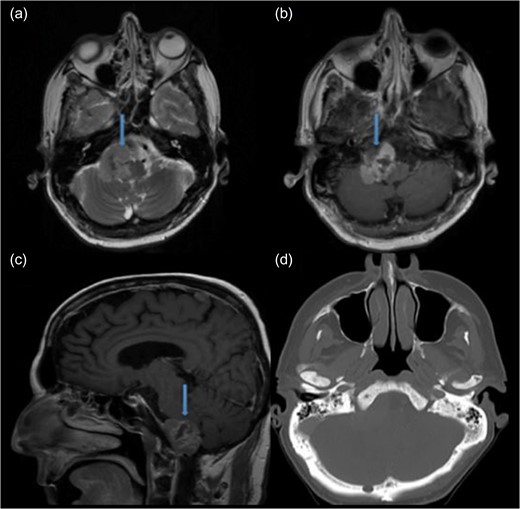

A 68-year-old male presented with 10-pound weight loss over the course of the last month as a result of progressive difficulty with swallowing. The neurological examination revealed a diminished gag and a weak cough reflex. His tongue was deviated to the right with significant atrophy. MRI of the head revealed a heterogeneous, contrast-enhancing mass that was hypointense on T1 and isointense on T2-weighted images. It was 3.7 cm in diameter, located at right anterolateral part of the FM, compressing the medulla oblongata, extending into the hypoglossal canal and jugular foramen, and encasing the posterior inferior cerebellar artery (PICA) (Fig. 1).

Preoperative MRI demonstrating an anterolateral right foramen magnum mass. (a) Axial T2-weighted MRI. (b) Axial T1-weighted contrast enhanced MRI. (c) Sagittal T1-weighted contrast enhanced MRI. (d) Axial CT image of brain shows no bone sclerosis or destruction.

Gadolinium-enhanced brain MRI is the gold standard to diagnose FM metastases [6]. The FM metastases show hyperintensity on T2 and hypointensity on T1 with variable contrast-enhancement. CT is also important to show bone destruction or sclerosis especially for prostate adenocarcinoma [6]. Interestingly, FM metastases can mimic subdural hematoma and meningioma [1, 9]. With the current case no bone invasion was detected by CT scans. Radiologically our case was similar to meningioma regarding the following features: isointensity on T2, hypointensity on T1 in MRI and no bone destruction or sclerosis in CT images (Fig. 1).